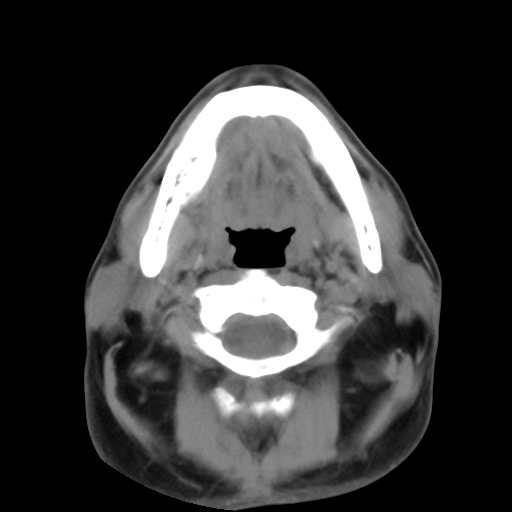

标题: CT24019:男,45岁,发现颈部肿物5个月。 [打印本页]

男,45岁,发现颈部肿物5个月,彩超示:双侧颈部及下颌部软组织增厚。

考虑双侧颈项部良性对称性脂肪增多症。